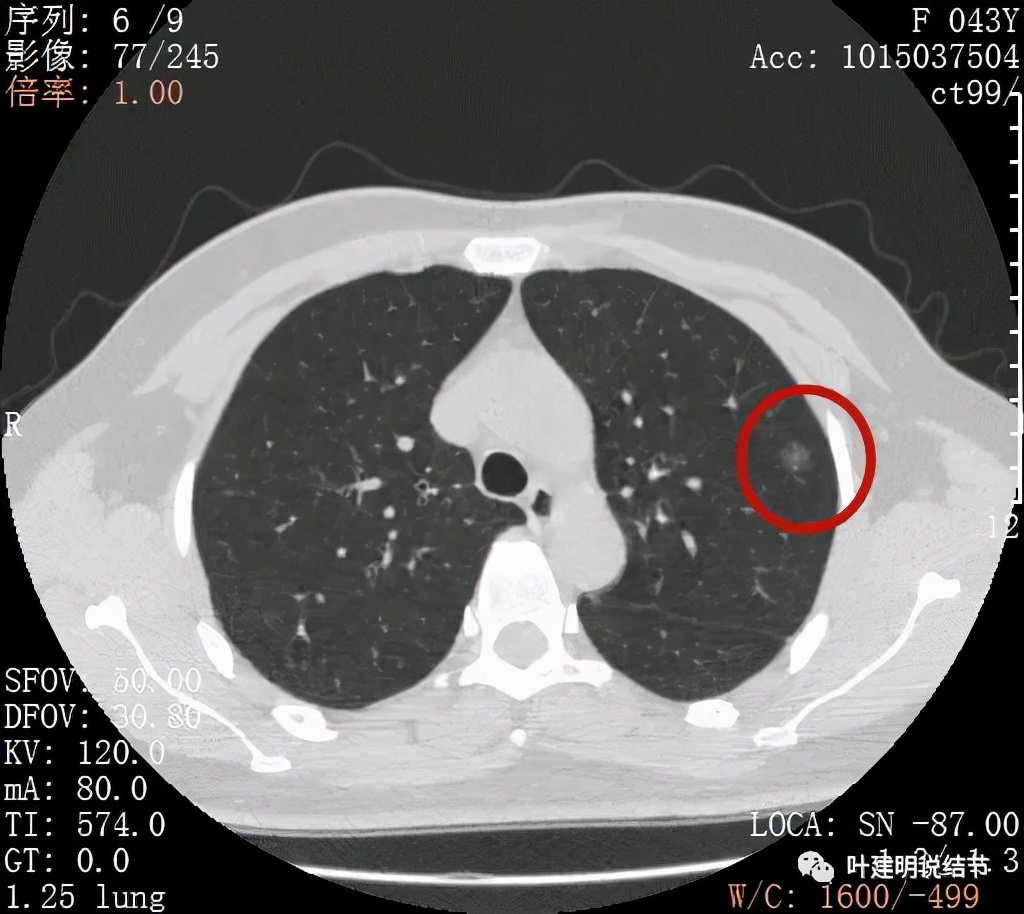

金华的某A,女性,今年43岁,检查发现左肺上叶结节2月余。其于当时说是在外院检查发现,到我门诊找我看过的(我是记不清楚了),大概是告诉她:考虑早期肺癌可能性大,但密度还低,边缘显模糊。让她再随访观察下再决定手术与否。这次送孩子上大学后,她马上来医院全面检查并若需要手术就决定手术了的。我们先来看她的平扫片子:

可见左肺上叶磨玻璃结节,边缘略显模糊,瘤肺边界不是很清,但总体上看,病灶轮廓仍是较为清楚的,而且有所层面有微小血管进入,病灶密度也不均匀,感觉有点杂乱。这种病灶如果随访了2个多月仍持续存在,也没多少变化的话,基本上要考虑肿瘤范畴的结节。为了看细节,我们建议其再查了靶扫描,图像如下:

病灶密度较低,膨胀性略,瘤肺边界在靶扫描上还是显得有些清晰的